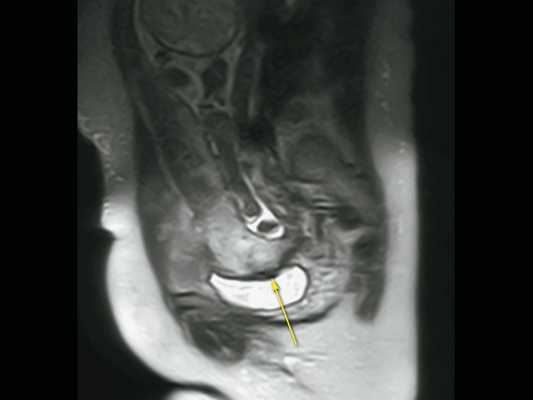

Дополнительное использование технологии стереоскопической визуализации кровотока (LumiFlow™) позволило визуализировать вовлеченность стенки мочевого пузыря беременной в конгломерат тканей аномальной плацентации (сосудистые мостики (rail sign) из миометрия сквозь серозный покров в стенку мочевого пузыря), то есть идентифицировать placenta percreta (PAS 3b). Проведенная в последующем МРТ констатировала полное предлежание плаценты с прорастанием в рубец, через все слои миометрия, шейку матки и цервикальный канал (рис. 8) и верхнюю стенку мочевого пузыря.

Рис. 8. Беременность 32 +4 нед. МРТ - Placenta percreta (PAS 3b). Зона прорастания плаценты в рубец через все слои миометрия в верхнюю стенку мочевого пузыря (стрелка).